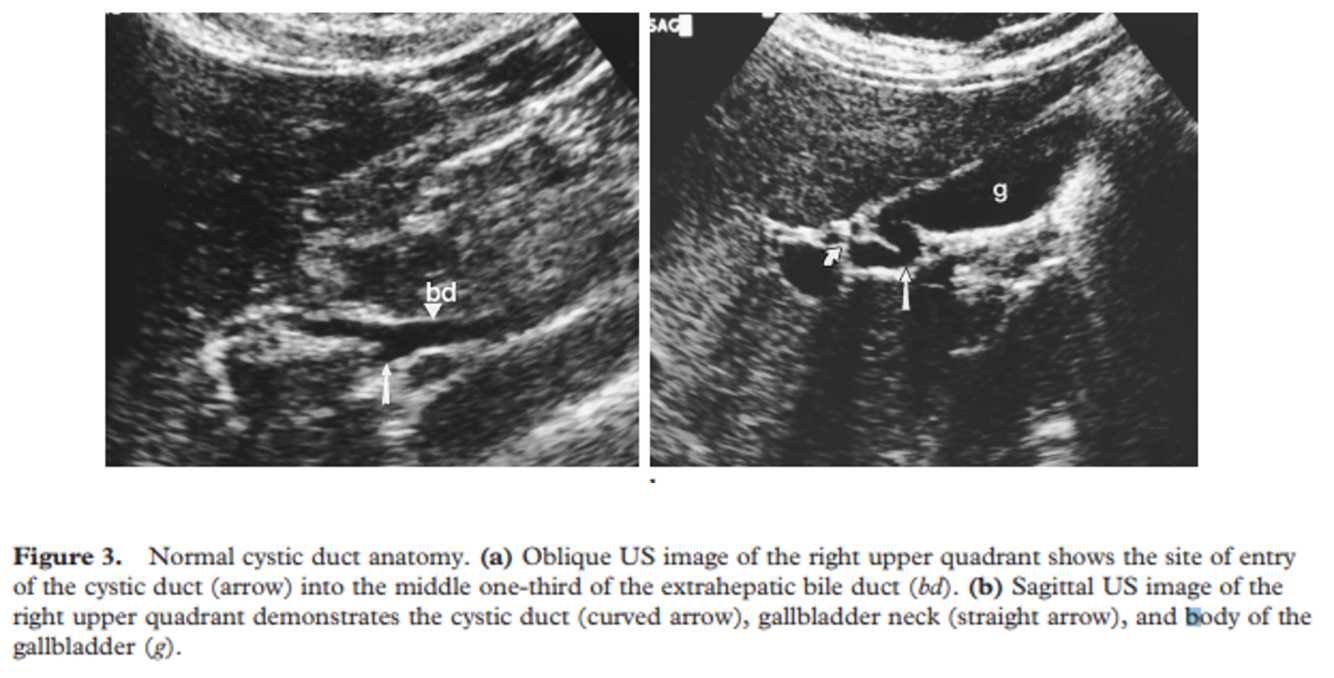

subvesicle bile duct –> can lead to persistent bile leak after cholecystectomy

what can lead to inadvertent common duct ligation in a cholecystectomy?

low insertion of the CBD